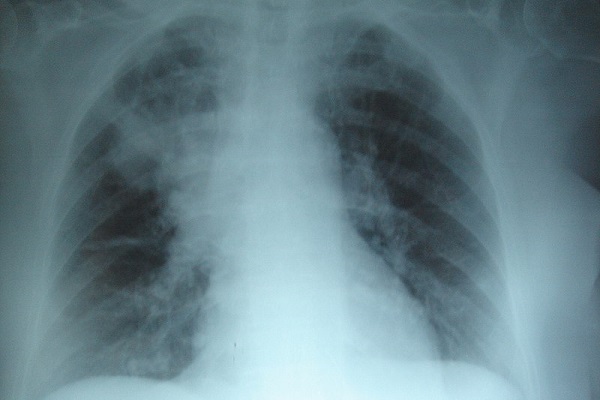

Anatomía radiológica

En esta rama de la anatomía se utilizan técnicas radiológicas o de imagen para estudiar las estructuras orgánicas más profundas.